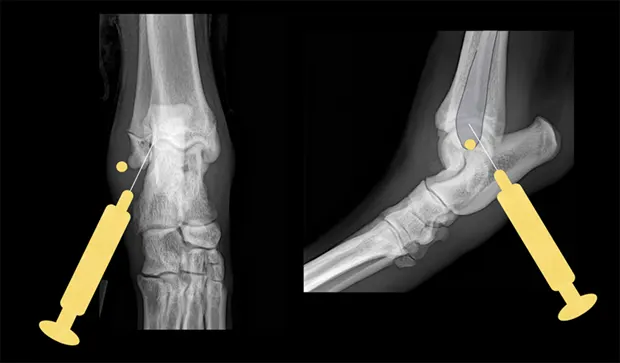

Tarsus

Place the patient in lateral recumbency with the affected limb on top. The lateral aspect of the joint usually provides the best yield of fluid because this area has the least villous synovium. In large-breed dogs, insert a 22-gauge, 1-inch needle in the caudodistal aspect of the distal fibula (lateral malleolus) at a 30°–45° angle from caudodistal to cranioproximal and in a distolateral-to-proximomedial direction. Another option is the dorsal joint pouch approach: place the needle between the tibia and talus to the medial or lateral side of the saphenous vein and extensor tendons.

Lateral and craniocaudal views of hock. Insert the needle just distal to the lateral malleolus at a 30°–45° angle in a craniomedial direction.

Carpus

Place the patient in lateral recumbency with the affected limb upward. The radiocarpal joint is the largest and easiest of the carpal joints to aspirate from the cranial side. Flexing the carpus by 45° opens the joint to facilitate needle entry. Palpate the cranial aspect of the distal radius, and insert the needle perpendicular to the long axis of the radius bone (parallel to the joint surface of the distal radius). Avoid penetrating the cephalic vein and tendons during the procedure by inserting the needle just medial or lateral to the midsagittal plane of the carpus.

Lateral view of carpus. Flex the carpus and insert the needle into the radiocarpal joint just distal to the distal extent of the radius bone.